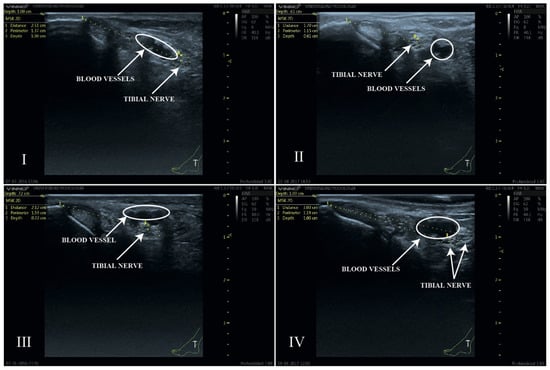

2.3.1. Classification of Nerve–Artery Relationship

- Type I: When, after outlining the perimeter of the tibial nerve, the nerve is located posterior to the posterior tibial artery.

- Type II: When, after outlining the perimeter of the tibial nerve, the nerve is located anterior to the posterior tibial artery.

- Type III: When, after outlining the perimeter of the tibial nerve, the nerve trunk is positioned beneath the vascular bundle, in a lateral position relative to the posterior tibial artery.

- Type IV: When more than one trunk corresponding to the tibial nerve is observed.